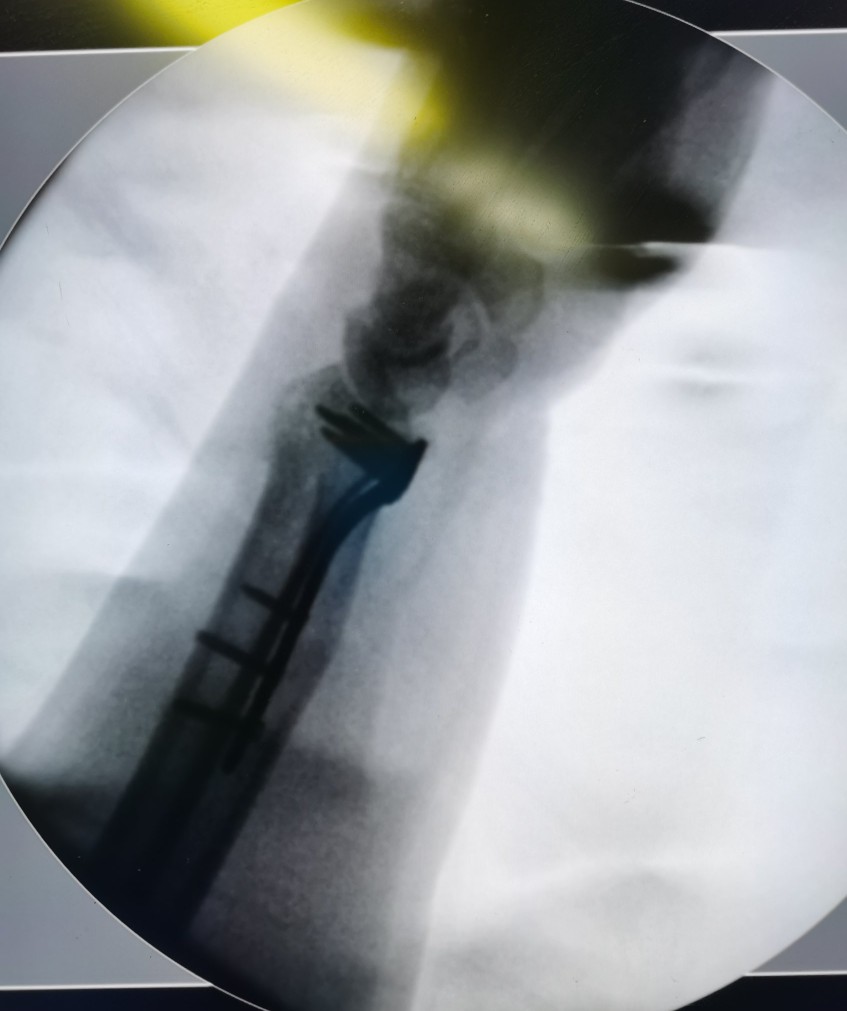

我们分开来讲,首先讲的是最常见的桡骨远端骨折。桡骨远端骨折里面最常见的骨折又叫colles骨折,或者叫克雷氏骨折,多见于老年人。手法复位+夹板固定的治疗方法对于大部分克雷氏骨折来说效果是确切的。手法复位的技巧很重要,一定要去大的正规医院。

当然,还有一些别的类型的桡骨远端骨折,我的建议是先手法复位,效果不好再考虑手术(包括复位效果不好的一部分colles骨折)。怎么看复位效果呢,做个腕关节的三维CT。主要看关节面怎么样,只要关节面还可以,角度(一般我们看掌倾角)还可以,就可以保守。关节外的有些小碎骨块可以不管。因为上肢关节负重比下肢要小的多。

比如复位确实不满意,关节面移位大,甚至关节面骨块有卡压,虽然病人年龄大,有糖尿病和冠心病,但是都能通过药物控制,而且有很好的麻醉医生,可以打臂丛麻醉,不用全麻,有娴熟的骨科大夫可以一个多小时把手术做完。这类病人完全可以选择手术治疗。